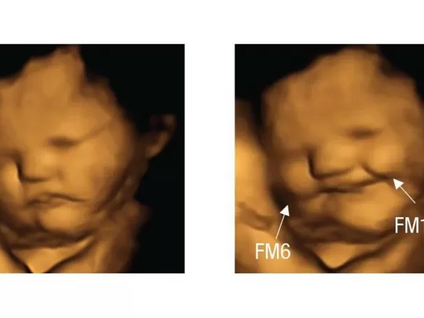

El estudio que mostró que los bebés en el vientre "sonríen" cuando sus mamás comen

Si el sabor de la col rizada te hace fruncir el ceño, no estás sola. Los científicos han descubierto que los fetos en el útero parecen...